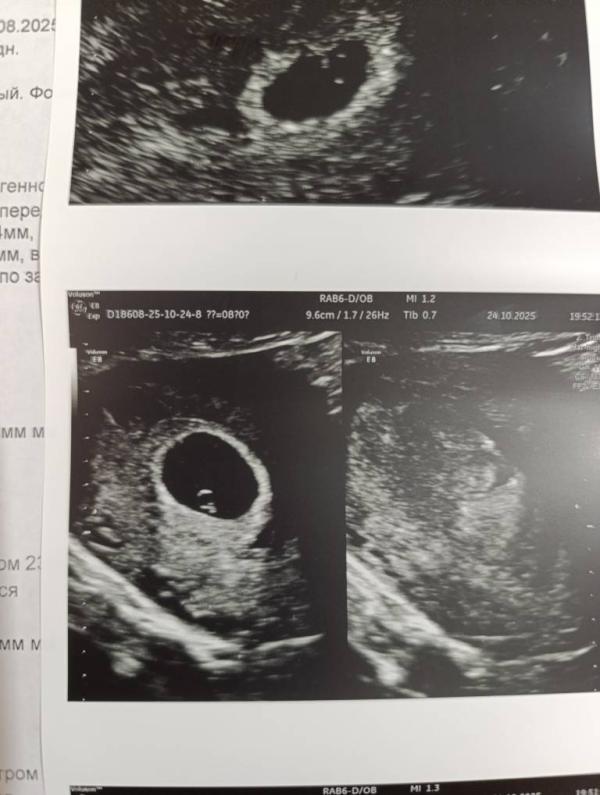

На память, моё колечко с бриллиантом 🥹 срок по узи 6 недель. Сердечко бьётся, посчитать ЧСС пока не смогли.